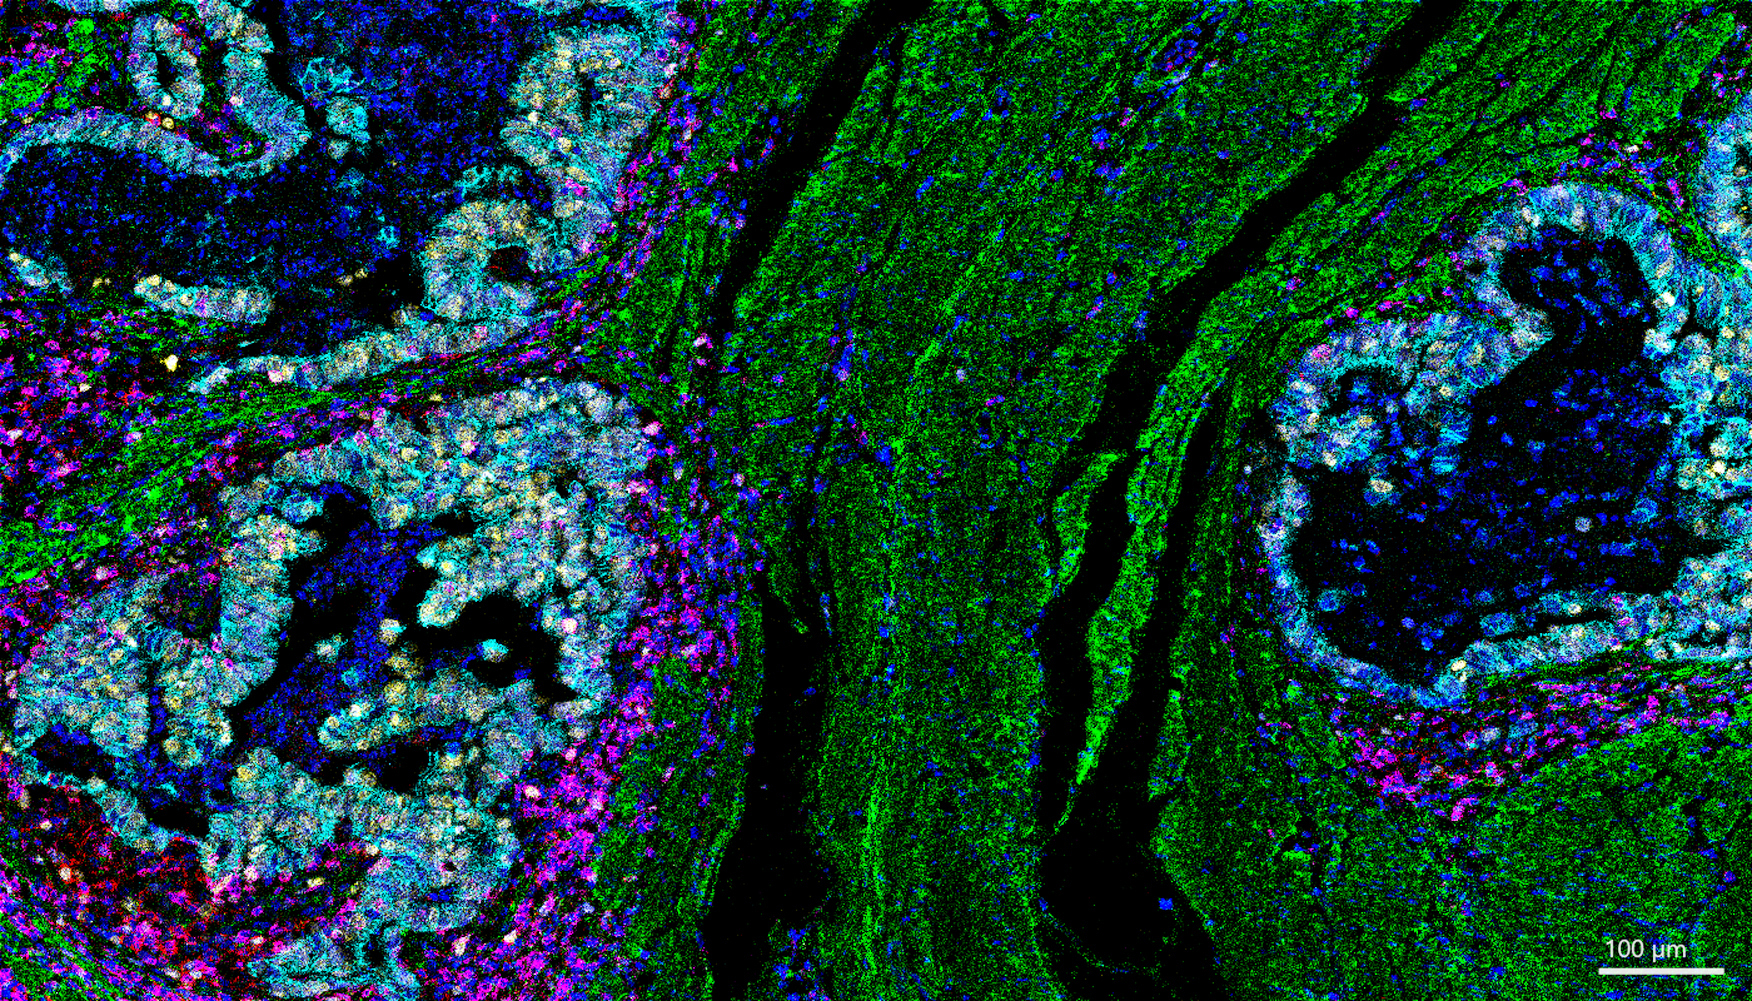

Für die Studie wurden Gewebeproben von 27 Patient*innen mit lokal fortgeschrittenem Speiseröhrenkrebs untersucht. Alle hatten eine sogenannte neoadjuvante Therapie erhalten – also eine Behandlung vor der Operation, meist in Form einer Chemotherapie oder kombinierten Strahlen-Chemotherapie. Dabei zeigte sich: Die Krebszellen selbst blieben erstaunlich stabil. Die Veränderungen fanden vor allem im Umfeld des Tumors statt – in den Immunzellen, dem Bindegewebe und den Signalwegen zwischen Zellen.

Besonders auffällig war: In Tumoren, die schlecht auf die Therapie ansprachen, fanden die Forschenden Hinweise auf eine sogenannte Immunflucht. Dabei verändert der Krebs bestimmte Oberflächenmerkmale, um vom Immunsystem nicht mehr erkannt zu werden. Auch hemmende Signale wie das Molekül PD-L1 waren bei diesen Patient*innen erhöht – sie gelten als mögliche Ziele für moderne Immuntherapien.